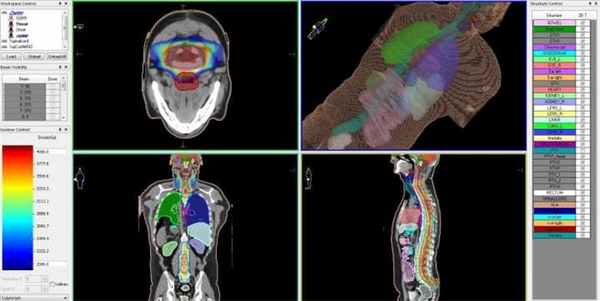

Для этого в процессе планирования лечения определяется требуемая форма и расположение объема, в котором будет сформирована зона равномерно высокой дозы ионизирующего облучения — она будет полностью совпадать с указанными лечащим врачом контурами опухолевого поражения. Составленная на основе данных КТ- и МРТ-исследований пространственная 3D-модель с указанием зон с минимальной и максимальной лучевой нагрузкой, передается в программный комплекс КиберНожа для расчета множества последовательно подаваемых с различных положений тонких лучей ионизирующего излучения. После этого пациент может начинать лечение эпендимомы на КиберНоже.

Лучевое лечение эпендимомы головного мозга на линейном ускорителе с принципом IMRT во многом соответствует принципу радиохирургического лечения опухолей на КиберНоже. Точность лучевой терапии, также как и при радиохирургии, обеспечивает контролируемая доставка высокой дозы ионизирующего излучения точно в объем опухоли, пространственные контуры которой составлены компьютерной системой планирования.

Перед тем как приступить к лечению, пациент проходит комплексную КТ- и МРТ-диагностику, на основании результатов которой лучевым терапевтом совместно с медицинским физиком составляется цифровая компьютерная трехмерная модель расположения опухоли и здоровых тканей вокруг нее, которые не должны быть подвергнуты облучению.

![]()

Эпендимома головного мозга — план лечения на линейном ускорителе, с распределением доз облучения для различных типов биологических тканей

Принцип действия IMRT-лучевой терапии состоит в том, что для каждой зоны, в соответствии с виртуальной компьютерной моделью, задаются максимальные и минимальные дозы ионизирующего облучения. Это позволяет доставлять в границы опухоли и пути ее метастазирования максимально высокие дозы излучения, необходимые для разрушения раковых клеток, а в зону расположения критических структур головного мозга — нулевые.

После того, как план лечения утвержден, пациенту назначается первый сеанс (фракция) лучевой терапии. Лечение проходит амбулаторно и не требует анестезии. Во время сеанса лучевой терапии пациент удобно располагается на специальном столе, а подвижная часть линейного ускорителя последовательно занимает различные положения, подавая необходимую дозу ионизирующего излучения в опухолевый очаг. Конфигурация каждого пучка излучения, точно повторяющего форму опухоли, формируется многолепестковым коллиматором, который управляется системой согласно заданному плану и контролируется ответственным врачом.

Лучевая терапия IMRT проводится таким образом, что наиболее высокие дозы облучения, необходимые для гибели раковых клеток, доставляются только в границы опухоли, а здоровые ткани вокруг нее поддаются наименьшему влиянию облучения. При этом наиболее важные структуры организма (ствол мозга, аорта, слюнные железы и др.) во время лучевой терапии абсолютно защищены — для них еще на стадии планирования лечения задается зона нулевого воздействия, так называемая «холодная зона».